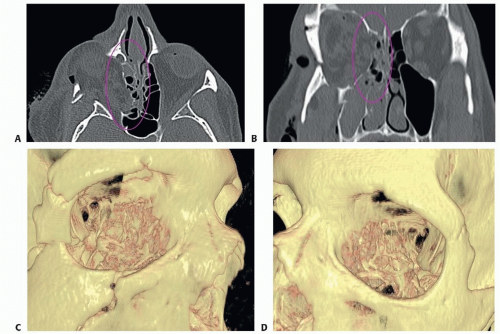

Fine-cut axial CT scan with mutiplanar reconstruction has great sensitivity and specificity for identifying medial orbital wall fractures. Two-dimensional axial and coronal views can accurately image the disruption of the medial orbital wall and demonstrate herniation of periorbital soft tissues into the ethmoid sinuses (FIG 3A,B).

Three-dimensional (3D) reconstructions of orbital CT scans are generally not helpful in diagnosing medial orbital wall fractures. The algorithms used by most 3D imaging software programs currently do not provide adequately detailed renderings of the surface anatomy of the thin curved medial orbital wall7 (FIG 3C,D).

![]() FIG 3 • Axial (A) and coronal (B) computed tomography (CT) imaging of the orbit demonstrating fracture of the (right) medial orbital wall with herniation of periorbital soft tissues into the ethmoid sinus (circled). C,D. 3D rendering of the same injury does not provide a detailed anatomic picture.